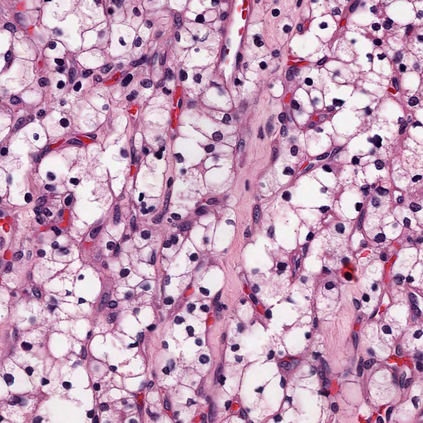

Due to the limitation of available labeled data, medical image segmentation is a challenging task for deep learning. Traditional data augmentation techniques have been shown to improve segmentation network performances by optimizing the usage of few training examples. However, current augmentation approaches for segmentation do not tackle the strong texture bias of convolutional neural networks, observed in several studies. This work shows on the MoNuSeg dataset that style augmentation, which is already used in classification tasks, helps reducing texture over-fitting and improves segmentation performance.

翻译:由于现有标签数据有限,医学图像分割是深层学习的一项艰巨任务,传统数据增强技术已证明通过优化使用少数培训实例来改善分割网络的性能,但是,目前的分割增强方法没有解决若干研究中观察到的动态神经网络的强烈纹理偏差问题。 这项工作显示在MONUSeg数据集中已经用于分类任务的样式增强,有助于减少纹理的过度装配,改善分割性能。